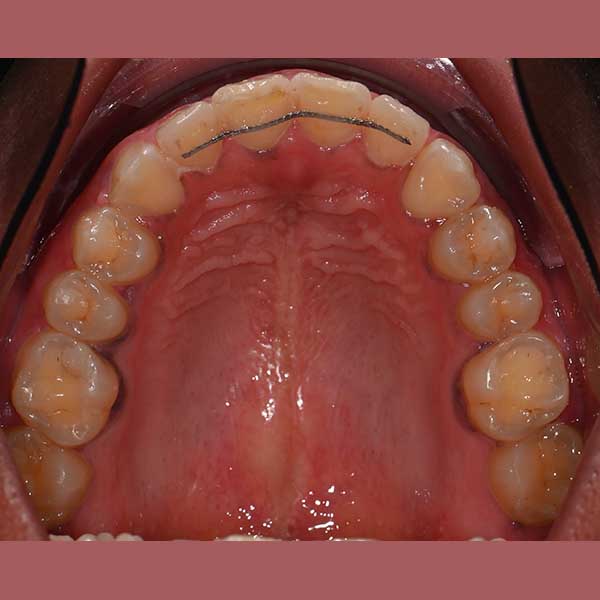

كما تظهر الصور، كانت النتيجة تحولاً جذرياً. تم سحب جميع الأسنان المنطمرة ورصفها في مكانها الطبيعي، وتم تصحيح وضع الأسنان السفلية. في نهاية العلاج، طلبت السيدة بنفسها وبكل ثقة أخذ صورة لابتسامتها الجديدة التي طالما حلمت بها.